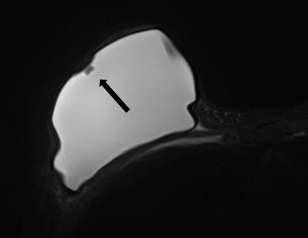

Minimally collapsed intracapsular rupture appears as a hypointense line that runs parallel to the fibrous capsule against the hyperintense extravasated silicone gelon silicone-sensitive MRI images, termed the “subcapsular line sign” (Figure 3).